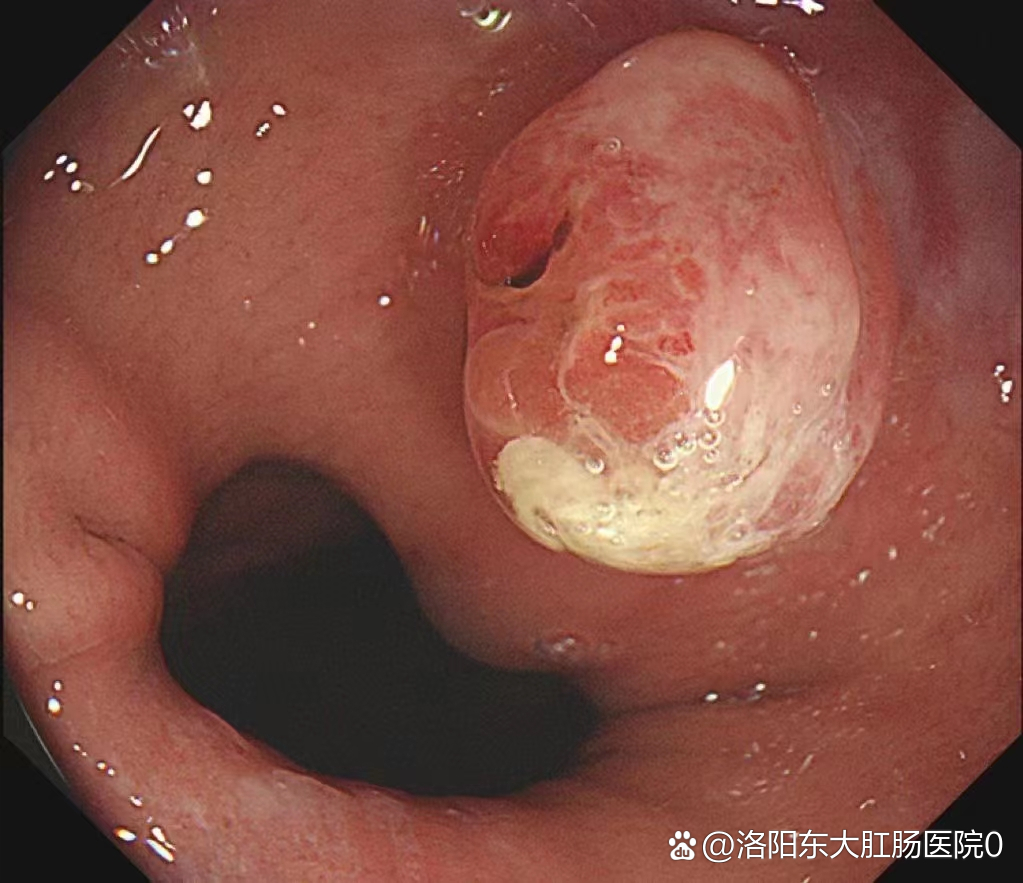

胃息肉是癌症的早期表现吗?

1、胃息肉不一定癌症的早期,并不是所有的胃息肉都会出现癌变大多数胃息肉都是良性胃息肉的发病原因至今不是特别清楚,通常认为与家族遗传基因幽门螺杆菌感染吸烟饮酒等因素有直接的关系临床上很多患者在早期根本不知道自己得了胃息...